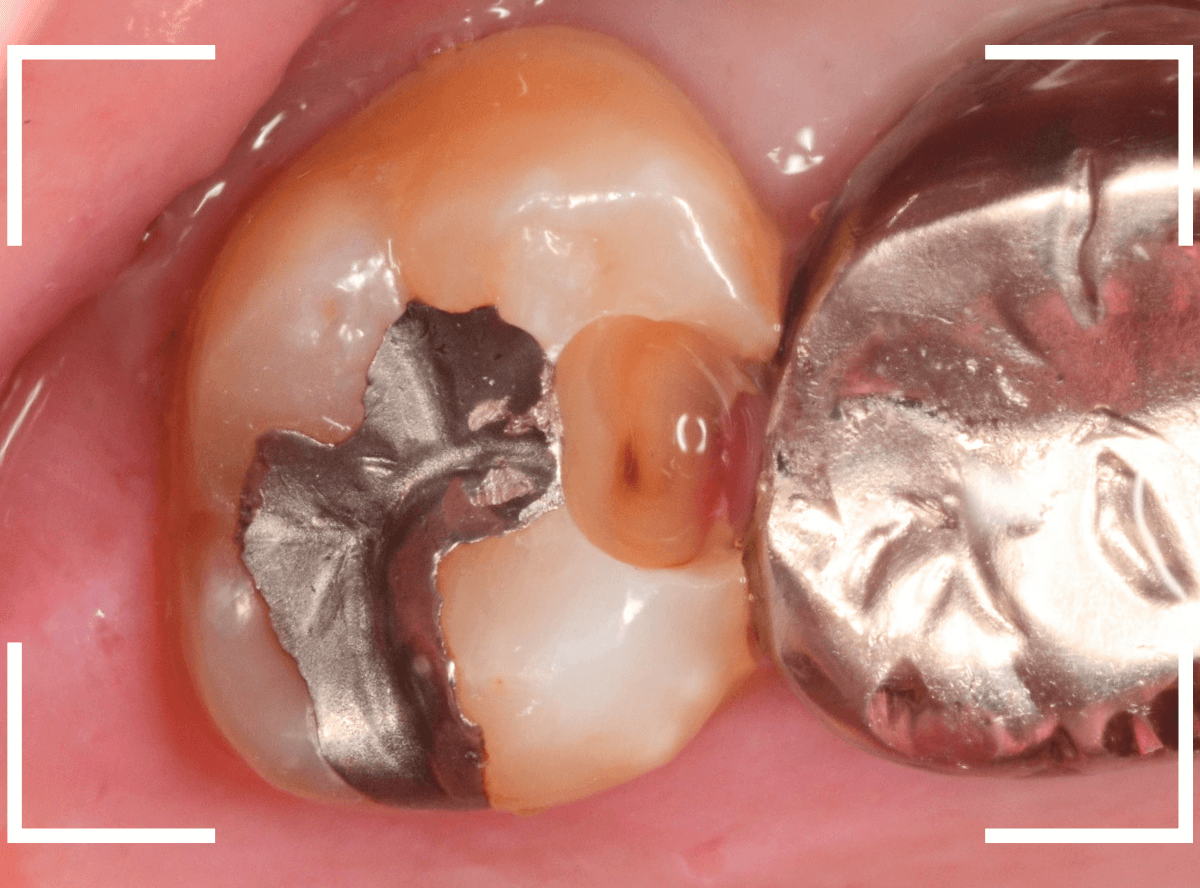

Case.25 レントゲン所見と目視を頼りに、虫歯治療

検査時に〇部、歯と歯の間の小臼歯部に虫歯らしき黒い影があるのが見つかりました。

かなり怪しいですが、メタル・インレーが入ってるので、それが透けている可能性もあります。

レントゲン写真で確認します。

レントゲンでは後ろの大臼歯部の方が虫歯になっているように見え、小臼歯部は問題ないように見えます。

まず大臼歯のインレーを外して、中を調べます。

あれ、インレー直下は虫歯がなさそうです。

レントゲン写真を頼りに、歯を削ると、虫歯が出てきました。

大臼歯の虫歯を削っていくと、手前の小臼歯まで虫歯がつながっていました。

やはり、黒い影は虫歯でした。これは深そうです。

メタル・インレーも外して、虫歯を除去します。

全ての虫歯を除去しました。

レントゲン写真では確認できませんでしたが、手前の小臼歯は深い虫歯でした。

このように、歯と歯の間の虫歯は、深い事が多いです。